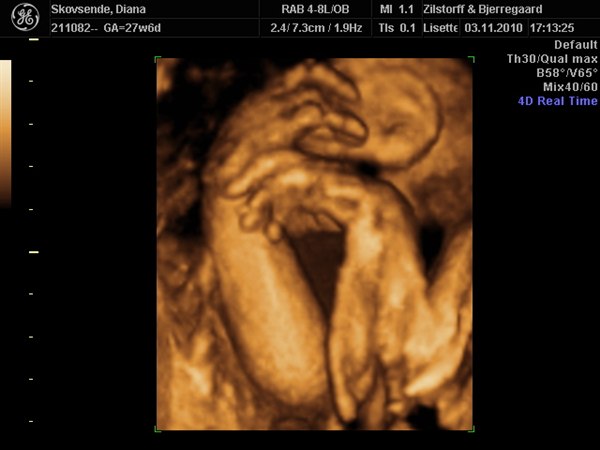

Idag har vi så været til 3D scanning og hun tjekket det hele og det så bare så fint ud de hele dog var min lille pige ikke særlig samarbejdsvillig så vi skal der ind igen på onsdag. Idag lå hun med hoved ned af og gemte sig bag sine finde hænder og vejer 948g så hun er en lille fin pige og hvis hun stadig vokser sådan kommer hun ud som en pige på 3200g det er jo fint Lucas kom ud som 3540g.

Nå men i får lige lidt billeder selv om det var mindre end lidt vi fik idag ;)

Wauw, hvor er det altså vildt, det man kan se på sådan nogle 3D-billeder. Jeg er vild med nr. 2 billede, der viser hende i profil. Kan I genkende jer selv i det?

Hvor dejligt at hun ser fin og god ud! Jeg kan da godt se at de små hænder helt dækker for ansigtet, men det er da fedt at i så har fået en ny tid!